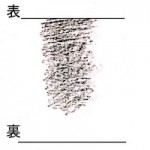

胸脇苦満ノ毒、浅薄ナル者ノ圖也。

按之而知ノ傳、圖ノ如ク、

脇下肋骨ノ端ヲ指ニテカヽゲミルニ、コタユルモノアリ。

是薄キ苦満ノ毒ナリ。

又、心下ヲ按テ少シクコタユルモノナリ。

是即痞鞕ナリ。世二積聚ト号スルモノ、此ノ證多シ。

原文の緑の下線部①〜③について

腹部の邪の現れ方についてです。

①厚深ナルモノハ見易ク

(邪が深くにあるものは見やすい)

②浅薄ナルモノハ見難シ。

(邪が浅くにあるものは見難い)

③毒浅薄ナルカ、如クニシテ、大二深キモノアリ。

(邪が浅くにあるようにみえても実は深くにある場合がある)

③は邪が腹底にあり、

表には現れないものである。

と記載されています。